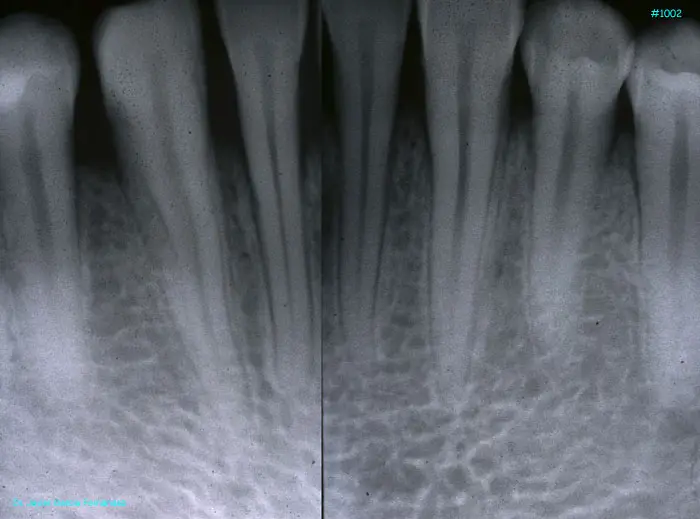

Atlas of Surgical Techniques in Periodontics. Chapter III. Atlas de Técnicas Quirúrgicas en Periodoncia